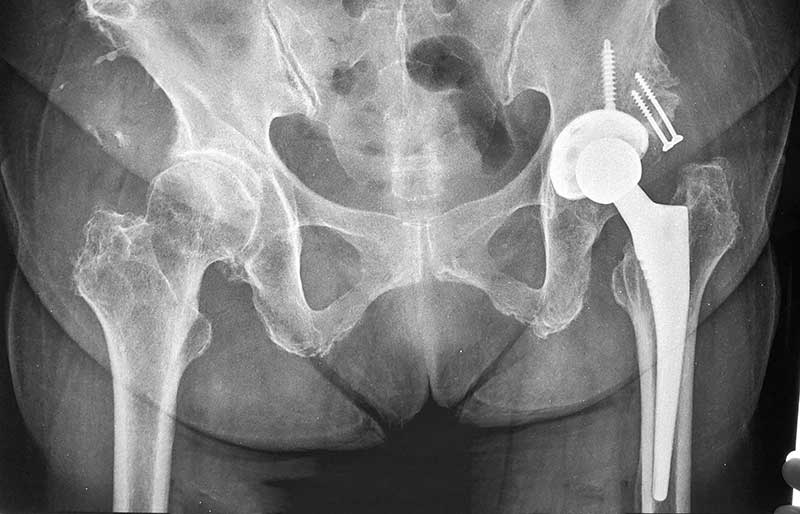

Operasi penggantian sendi panggul adalah suatu operasi untuk mengganti sendi panggul yang rusak dengan sendi buatan yang disebut prosthesis. Penyebab utama kerusakan sendi panggul adalah osteoartritis (baca penjelasan tentang “Osteoartritis”) dan sendi panggul adalah sendi terbanyak kedua setelah lutut yang terserang penyakit ini.

Operasi penggantian sendi panggul merupakan pengobatan terbaik untuk osteoartritis panggul stadium yang berat. Ada empat tujuan operasi ini, yaitu menghilangkan rasa sakit sendi yang telah rusak, memperbaiki lingkup gerak sendi yang sebelumnya kaku dan terbatas, mengembalikan kemampuan penderita melakukan aktivitas harian tanpa rasa sakit, dan meningkatkan kualitas hidup sehingga penderita kerusakan sendi dapat menjalani hidup secara aktif bebas dari nyeri sendi panggul.